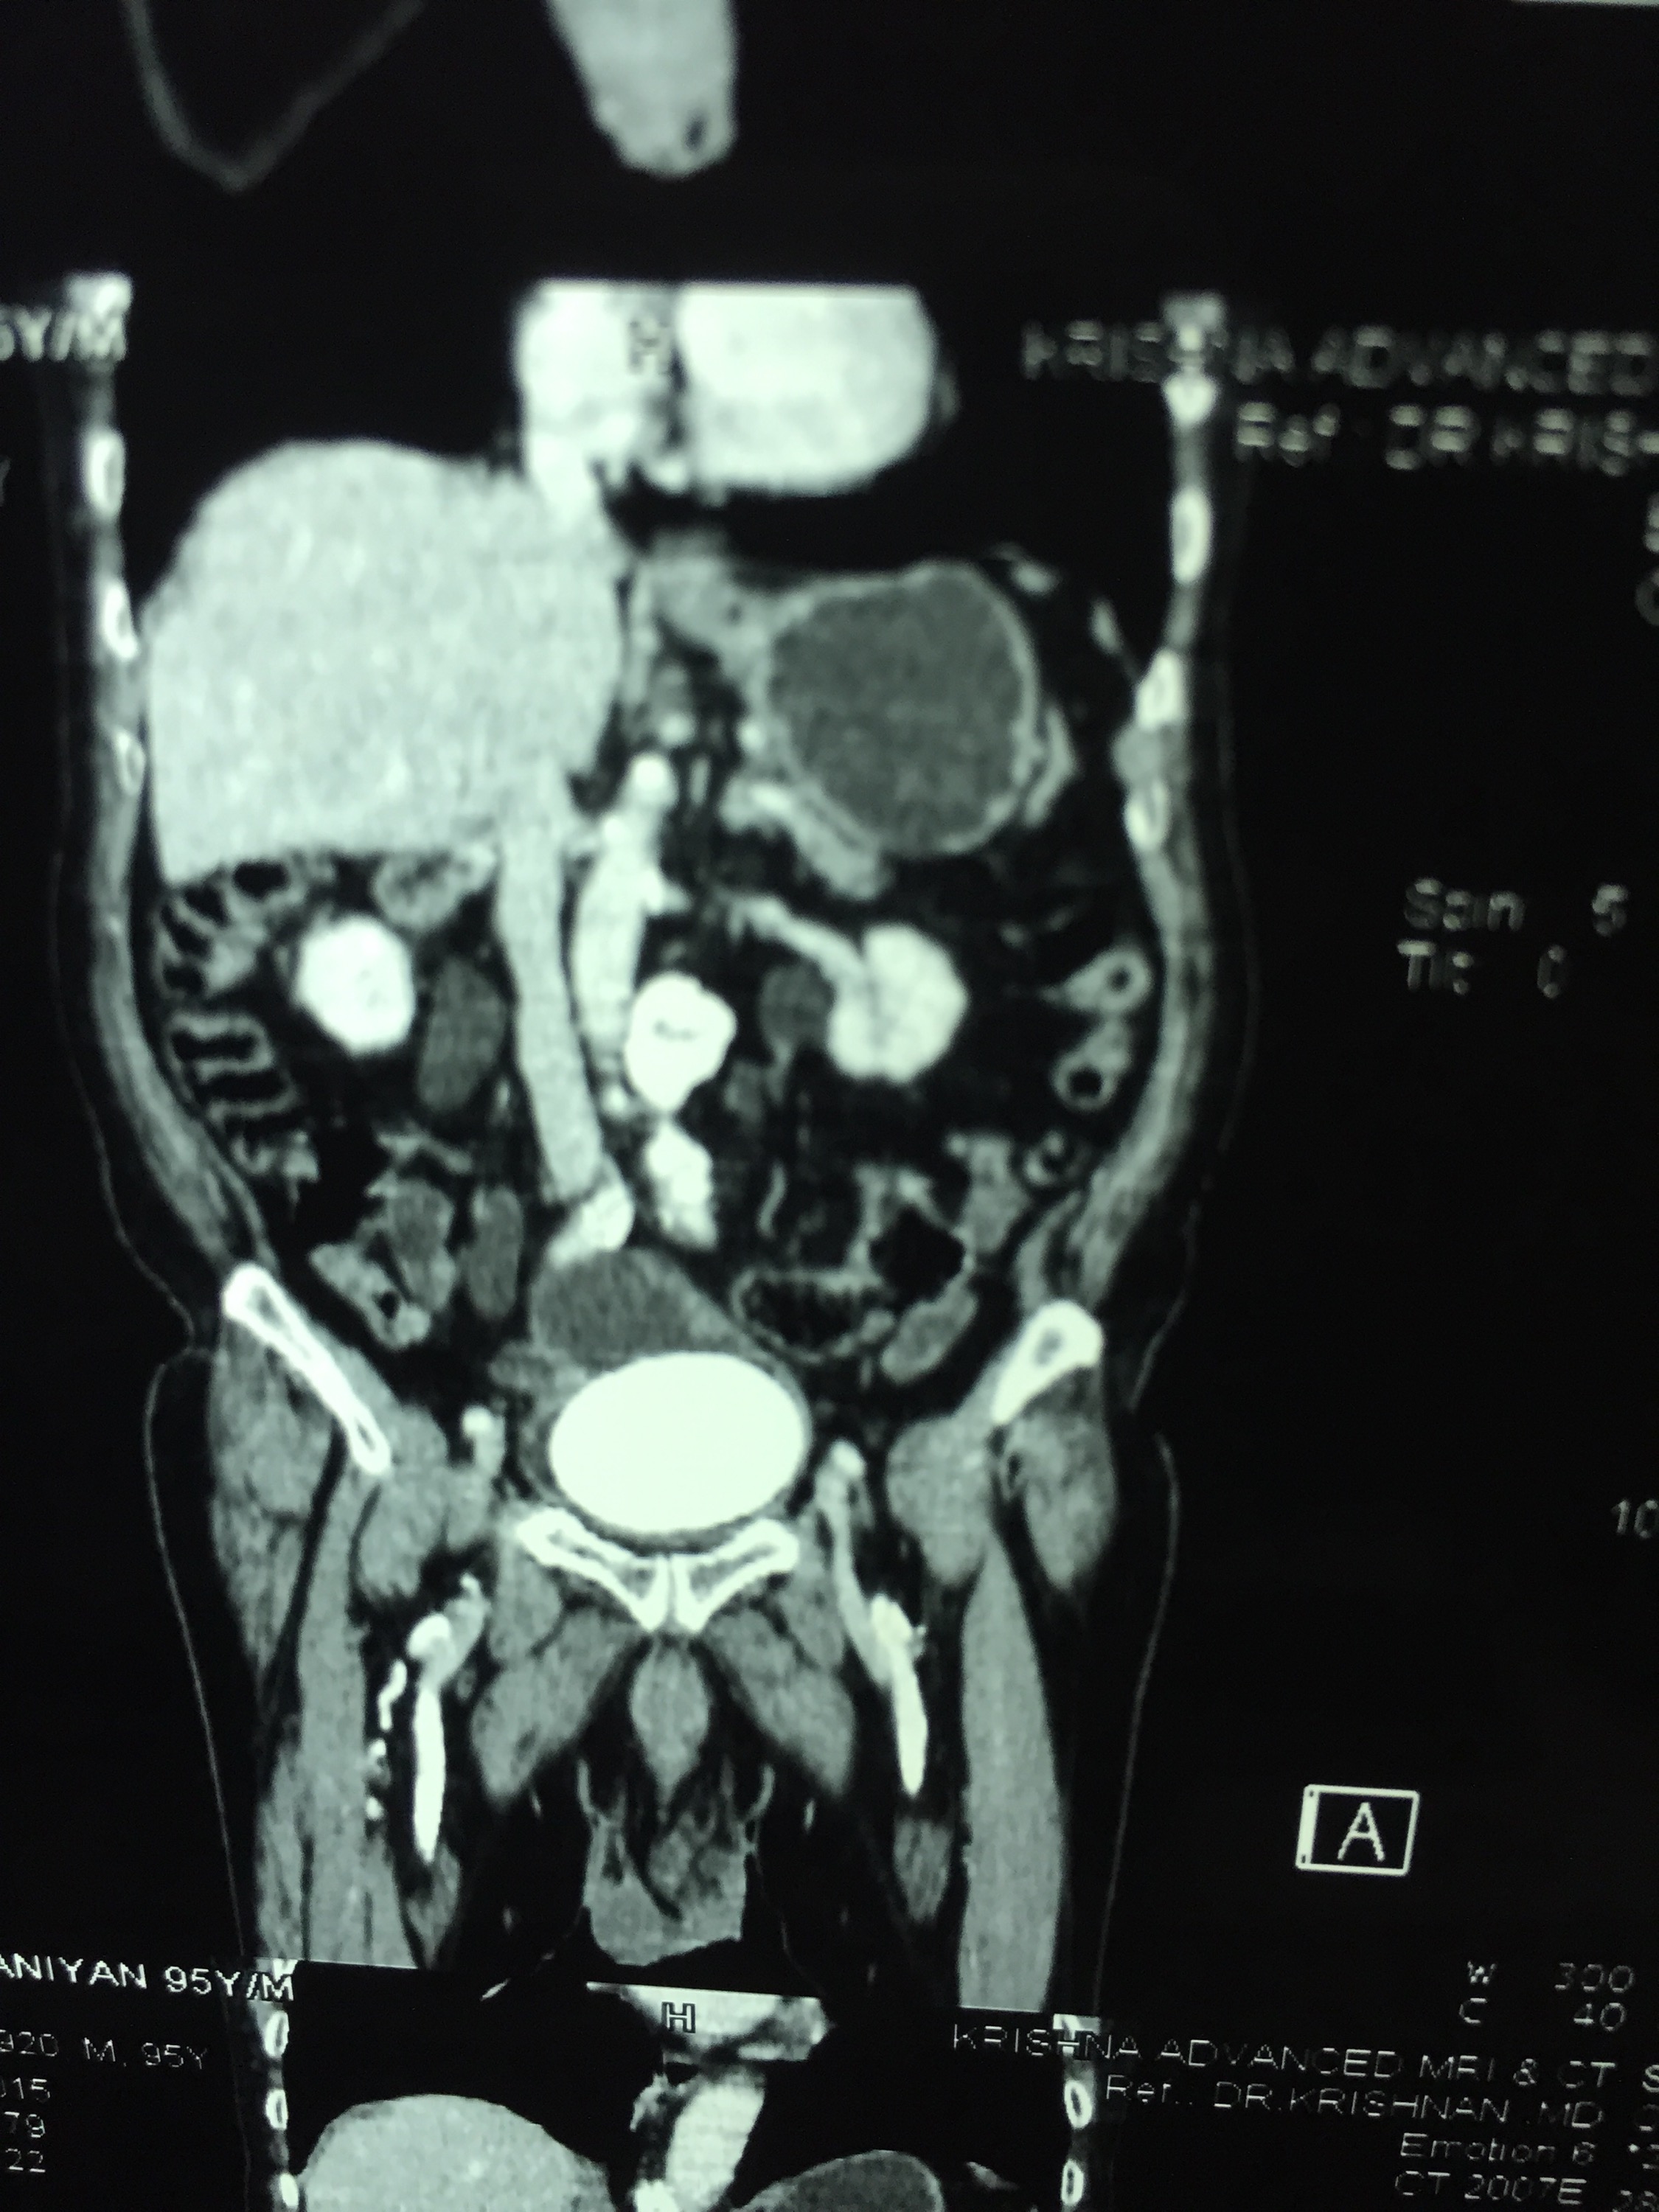

CT scan confirmed the ultrasound findings :

LARGE CALCULUS IN THE URINARY BLADDER WITH MULTIPLE DIVERTICULAE IN THE BLADDER “

The X-ray and the CT scan pictures are given below.